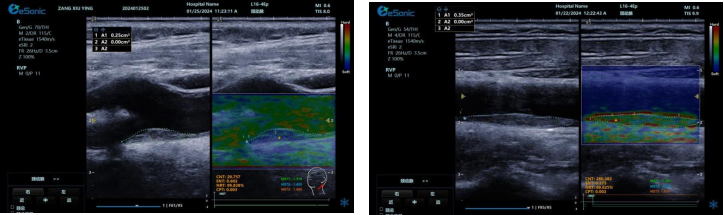

(二)RawVisionTM Plaque技术(RVP)

RVP 是世界领先的颈动脉斑块自动定量分析成像模式,依托 RawVisionTM原数平台强大的原始射频数据采集与分析能力。其优势显著:

? 可视化呈现方面,能分析斑块在特定条件下内部纹理变化,生成可视化参数成像。医生可依据颜色辨别易损与稳定斑块,并进行定量测量。

? 定量评估上,提供 CNT、ENT、NRT、CPT 等指标和参数,为监测老年颈动脉斑块风险提供客观准确依据。

? 借助 AI 自动分析,可快速筛选诊断,提升脑卒中筛查效率,有望重塑易损斑块临床诊断流程。

? 具备技术升级潜力,支持高端科研,能挖掘更多诊断参数,满足临床需求。

相比传统超声弹性成像技术,RVP 利用颈动脉搏动采集数据,避免了操作者施压等主观因素干扰,数据处理更精准,结果重复性佳,不受操作者差异影响。